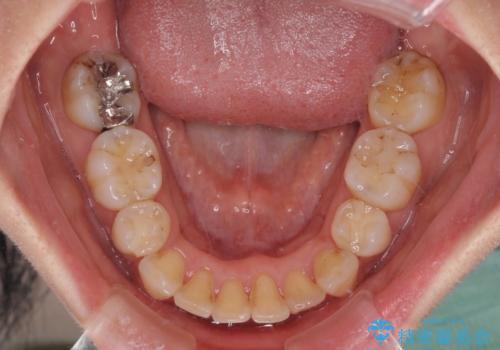

- 2年8ヶ月

- 上下の出っ歯を気にして来院された患者様です。

口元を積極的に引っ込めるために、上下左右の第一小臼歯を4本抜歯することとしました。

元々ディープバイトのため、スペースを閉じている期間に上下前歯が接触してしまい、治療期間が想定よりも伸びてしまいました。